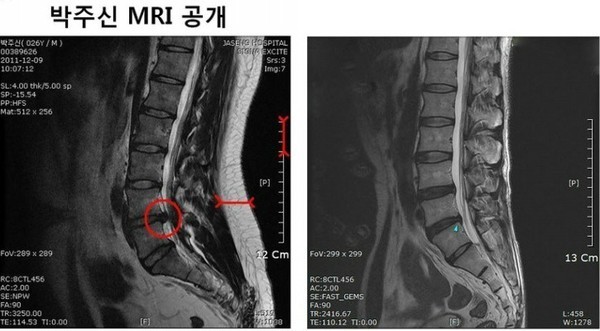

- ▲ 무소속 강용석 의원이 공개한 박원순 시장 아들 박주신의 MRI 사진(좌) 키 173cm 63kg 박주신과 같은 체형을 가진 허리디스크 환자의 MRI 비교. 전문의들은 좌측 사진에 대해 90kg 이상 고도비만 환자의 것이라는 분석을 내놨다. ⓒ강용석 의원실